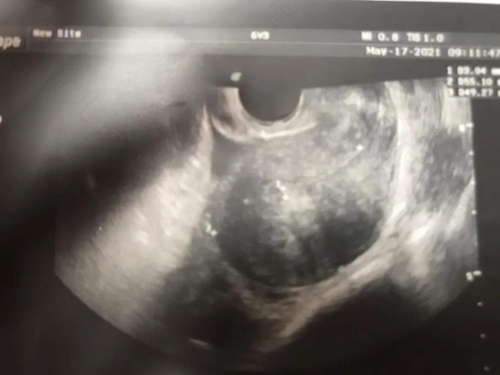

b超检查能够直观的对宫腔进行观察,不仅能够更好的了解胎儿在子宫内的发育情况,还能够对诸多宫腔疾病做出诊断。但是很多女性对b超检查结果的专业名词一头雾水。那么,b超显示子宫肌核是什么?

b超显示子宫肌核多表示女性的子宫内有肌瘤存在。子宫肌核是生长于子宫肌层的包块及良性肿瘤,多是由于女性体内雌激素水平较高等原因而引发,个体较小的子宫肌核通常不会对女性的健康造成伤害,所以不用进行特殊治疗,可通过定期的复查来密切关注其增长情况。